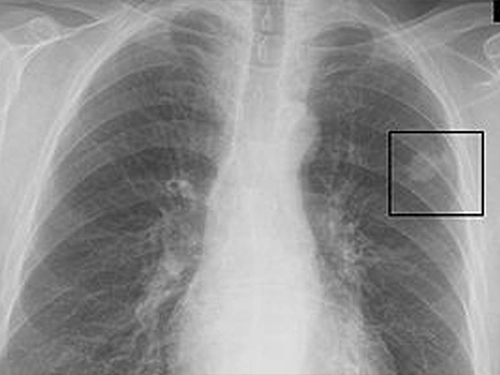

Akciğerde leke, akciğer dokusunda normalden farklı olarak görülen ve genellikle akciğer röntgeni veya bilgisayarlı tomografi (BT) gibi görüntüleme yöntemleriyle tespit edilen anormal oluşumlardır. Bu lekeler, boyut, şekil ve yoğunluk açısından farklılık gösterebilir ve çeşitli sağlık sorunlarının belirtisi olabilir. Akciğerde leke neden olur sorusunun cevabı oldukça geniştir; enfeksiyonlar (zatürre, tüberküloz), iltihaplanmalar, tümörler (iyi huylu veya kötü huylu), yabancı cisimler, skar dokusu ve nadir görülen bazı hastalıklar bu lekelere neden olabilir. Akciğerde leke tespit edildiğinde, altta yatan nedeni belirlemek ve uygun tedaviyi uygulamak için ileri tetkikler gerekebilir.

Akciğerde leke, genellikle akciğer röntgeni veya bilgisayarlı tomografi (BT) gibi görüntüleme testlerinde görülen ve normal akciğer dokusundan farklı bir görünüm sergileyen alandır. Bu lekeler, çeşitli nedenlerle ortaya çıkabilir ve her zaman ciddi bir sorunu işaret etmeyebilir.

Akciğerde leke terimi, tıbbi bir terim olmaktan ziyade, halk arasında kullanılan bir ifadedir. Tıp dilinde, akciğerdeki bu tür görünümler genellikle "nodül", "infiltrasyon" veya "opaklık" gibi terimlerle ifade edilir.

Akciğerde "leke" olarak adlandırılan durum, radyolojik görüntüleme (röntgen, BT) ile saptanan ve normal akciğer dokusundan farklı görünen alanları ifade eder. Tıbbi literatürde bu görünümler için daha spesifik terimler kullanılır. "Leke"nin türü, altta yatan nedene ve görüntüleme özelliklerine göre değişir. Yaygın akciğer leke türleri şunlardır: